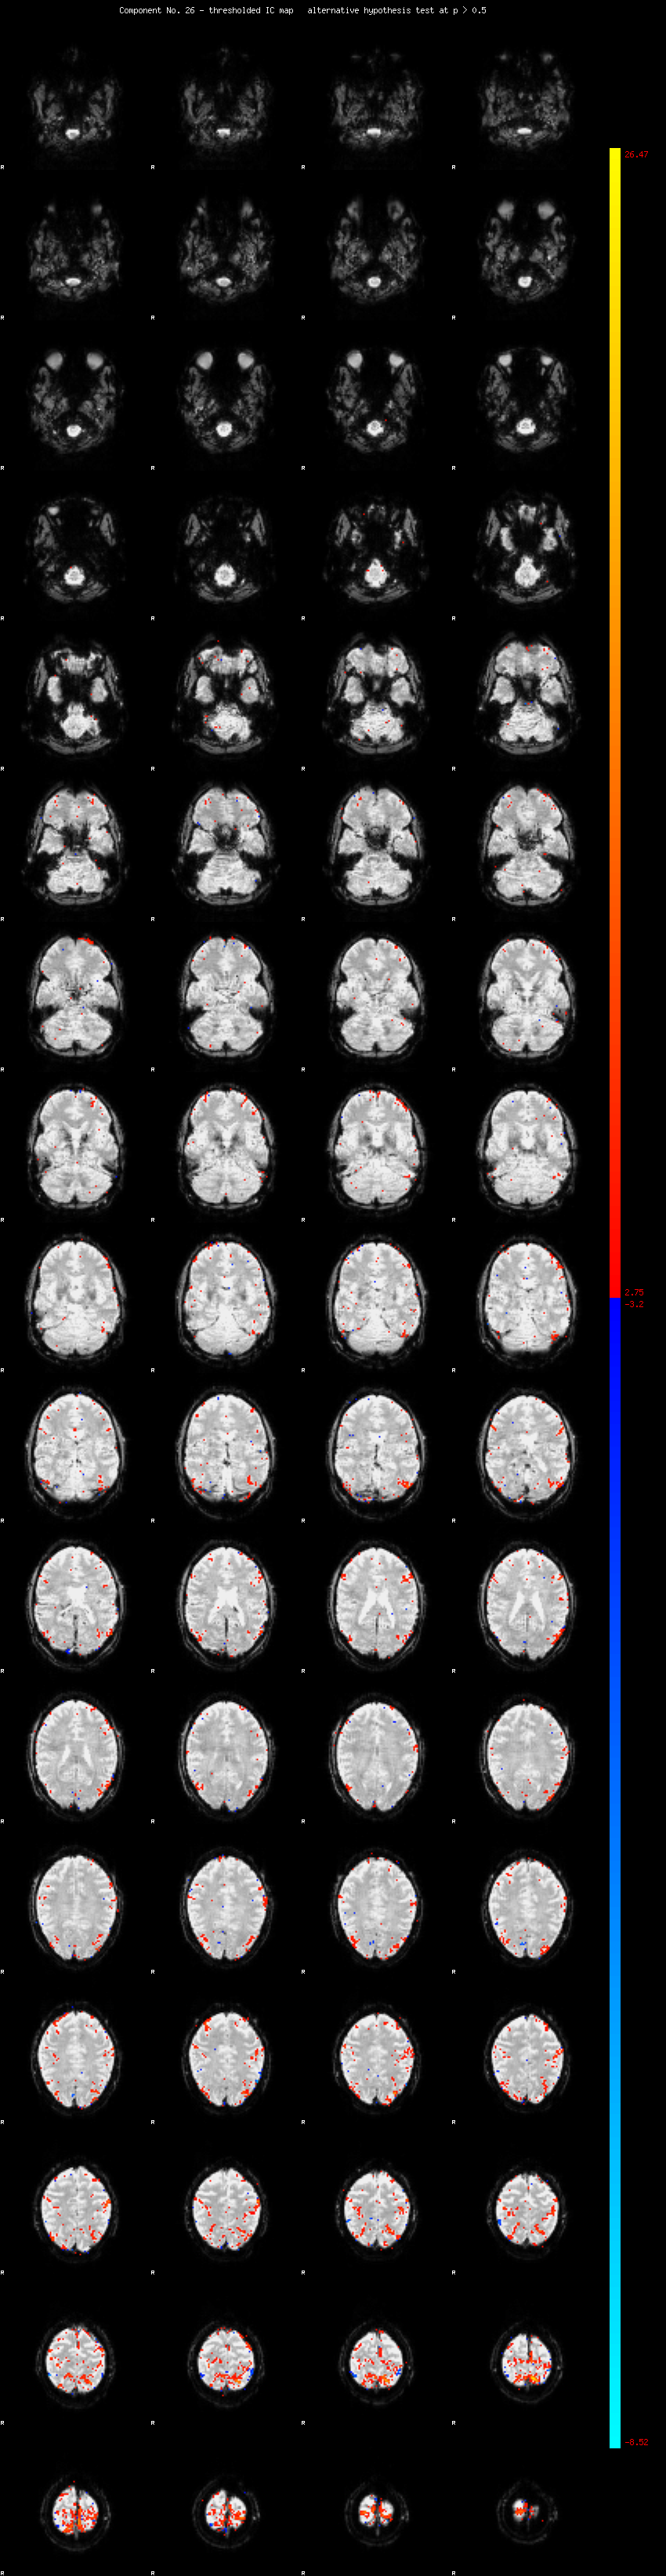

MELODIC Component 26

1.26 % of explained variance;     0.84 % of total variance